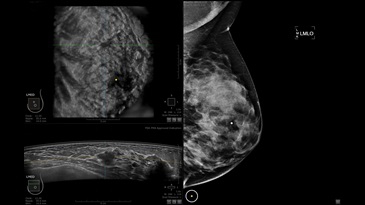

GE INVENIA ABUS – это современный УЗИ аппарат, который создан для точной и эффективной диагностики сканирования с высокой плотностью молочных желез. Выявляемость патологий раковых и предраковых стадий заболевания составляет 55%, что в конечном счете позволяет ставить врачу точные и своевременные диагнозы. Традиционные методы использования маммографии не показывают такой выявляемости, ограничиваясь лишь 3-38%.

УЗИ-аппарат GE INVENIA ABUS позволяет проводить максимально операторонезависимые процедуры, что значительно снижает риск неправильной постановки диагноза и сопутствующие издержки на обработку информации. Система готовит отчет в течение 3-х минут после сканирования, это безусловное преимущество по сравнению с обычным УЗИ сканером.

• датчик с изогнутой апертурой для качественного исследования

• сканирование одной грудной железы в трех проекциях не более 60 сек.;

• обработка результатов за три минуты.

Возможности встроенной УЗ-системы:

• Увеличение или уменьшение степени сжатия грудной железы;

• Функция автоматического сканирования активируется одним нажатием;

• Возможность отмены сканирования;

• Глубина проникновения УЗ-лучей – до 50 мм;

• Одно детализированное изображение можно получить менее чем за 1 минуту

• Многорядная светодиодная подсветка;

• Встроенный сверхширокий вогнутый датчик С15-6ХW.

Области применения: ультразвуковой скрининг заболеваний молочных желез.